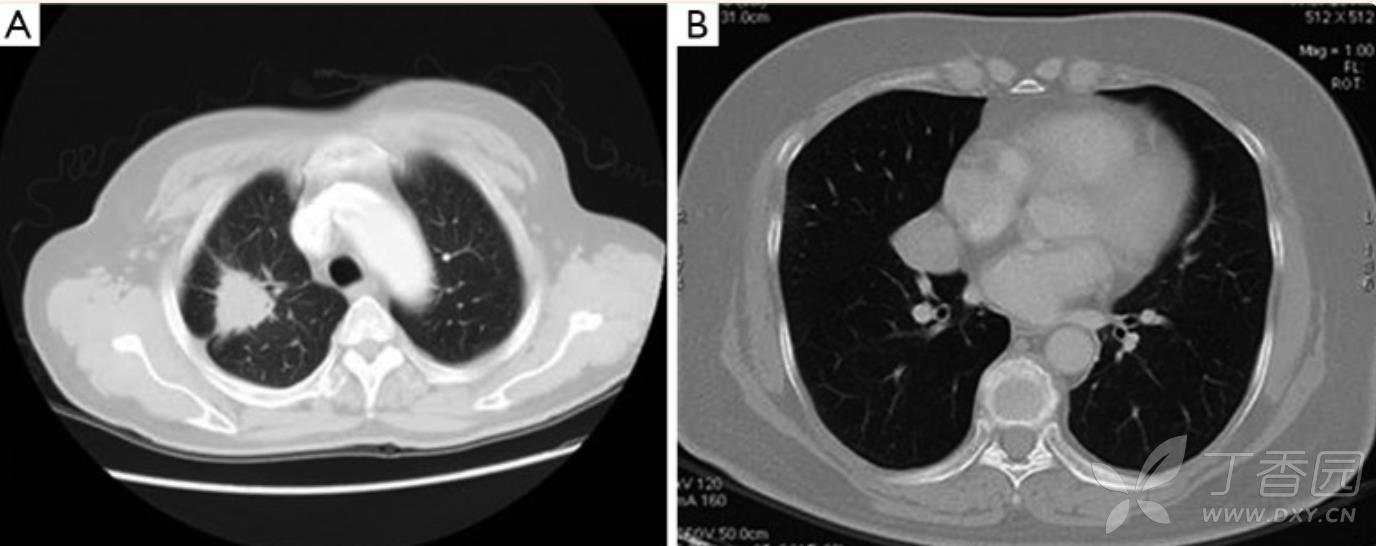

A,男性,61岁,右上肺结节。CT显示:结节呈小叶状,边缘有小毛刺,有血管聚集。

B,男性,66岁,右肺中叶结节。CT显示:结节边缘光滑,无分叶,无血管聚集。